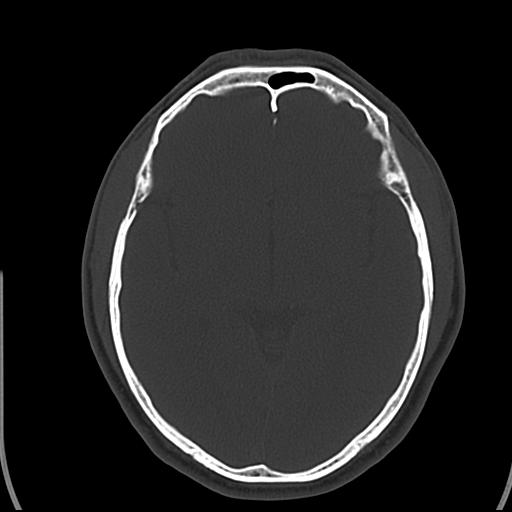

头皮下高密度结节影???临床上在老年男性比较常见。大家看看是什么?成因是? 本例患者,男性,51岁。外伤来诊。无染发史及发根植入史。

皮下钙化点

没见过,可能为毛囊钙化。

考虑钙化。